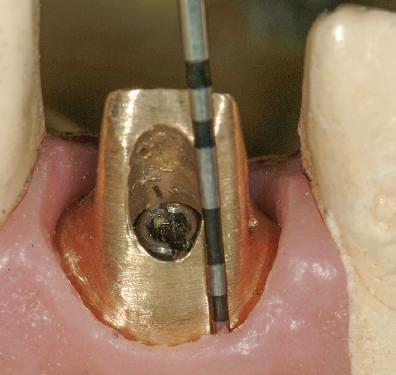

Raţionamentul începe cu motivul pentru care ar trebui folosit un anumit tip de bont implantar. Se pare că există o cerere pentru fabricarea mai degrabă a restaurărilor fixate cu şuruburi decât a unui bont şi a unei coroane cimentate. Cel mai evident scop al utilizării bontului constă în obţinerea corectării implantului aflat într-un unghi care ar transforma orificiul de acces al şurubului într-un dezavantaj estetic. Cel mai frecvent se întâlneşte în cazul dinţilor maxilari frontali, unde arhitectura osoasă tinde să creeze o inclinare vestibulară a implantului pentru a evita perforaţia apicală a peretelui vestibular. De aceea, implantul este înclinat spre latura vestibulară şi lasă orificiul de acces pentru şurub fie prin muchia incizală, fie pe suprafaţa palatinală a restaurării (fig. 6, 7).

6, 7. Aspectul unei proteze parţiale fixe pe implanturi cu fixare cu şurub, prezentând plasarea ideală a implantului pentru accesul lingual la şurub.